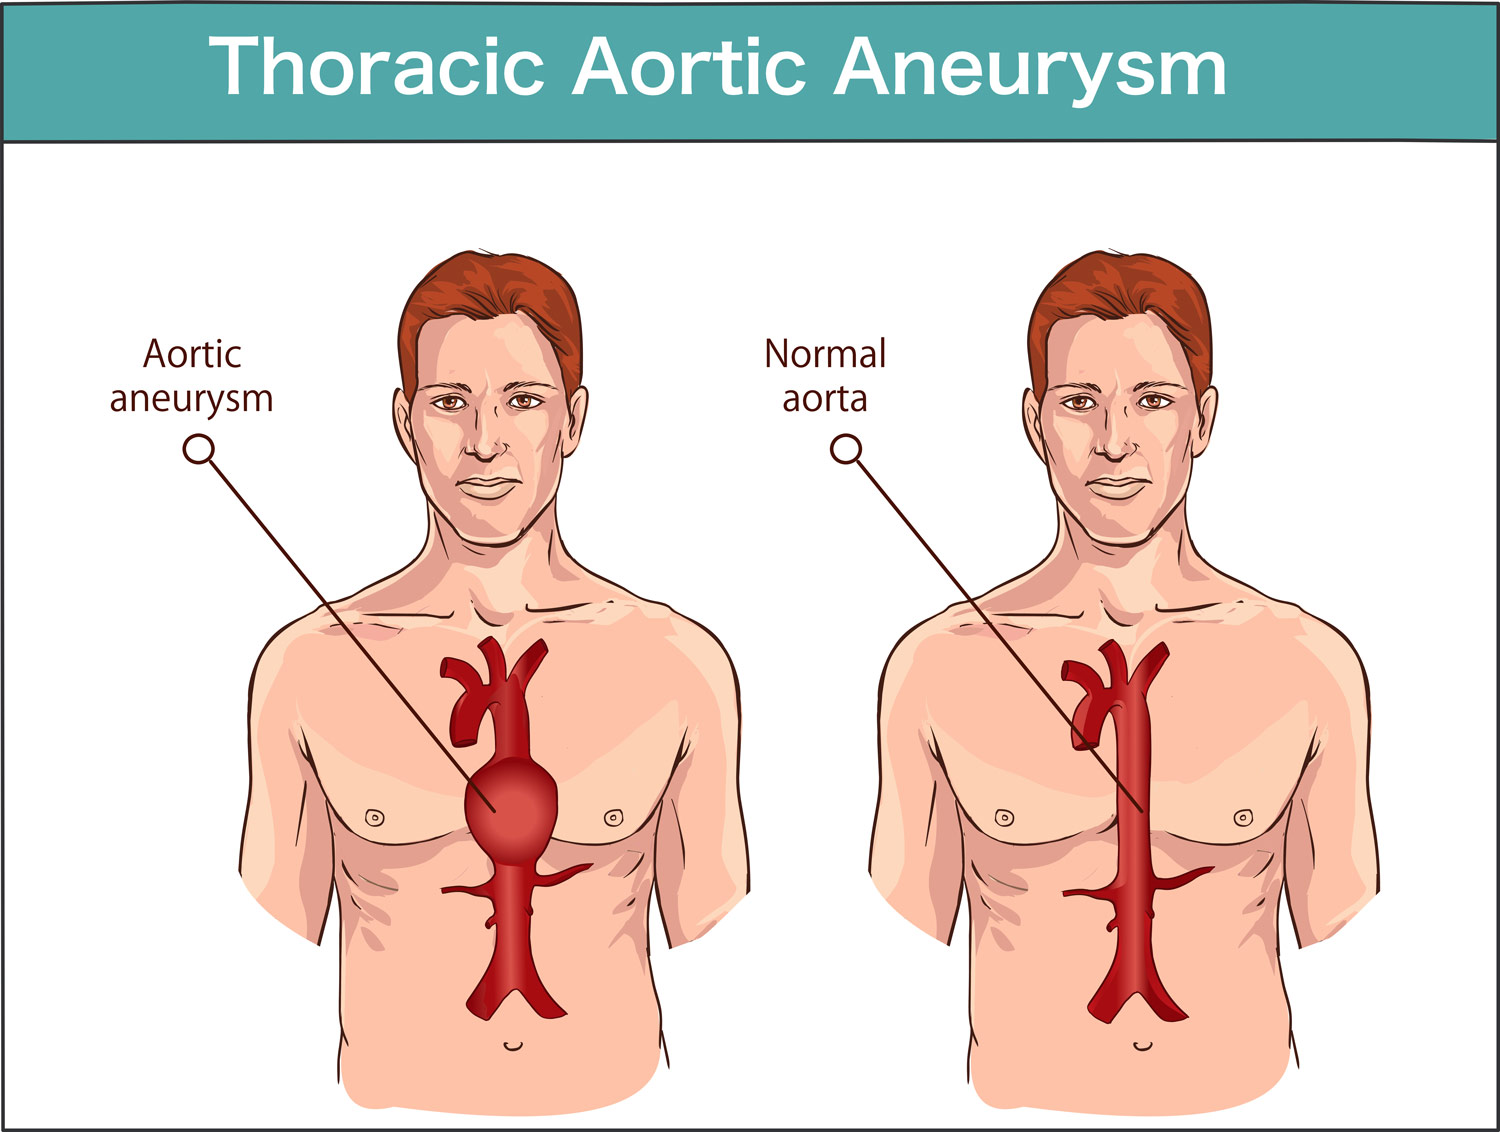

ANEURYSM

ANEURYSM

Thoracic Aortic Aneurysm Symptoms Treatment